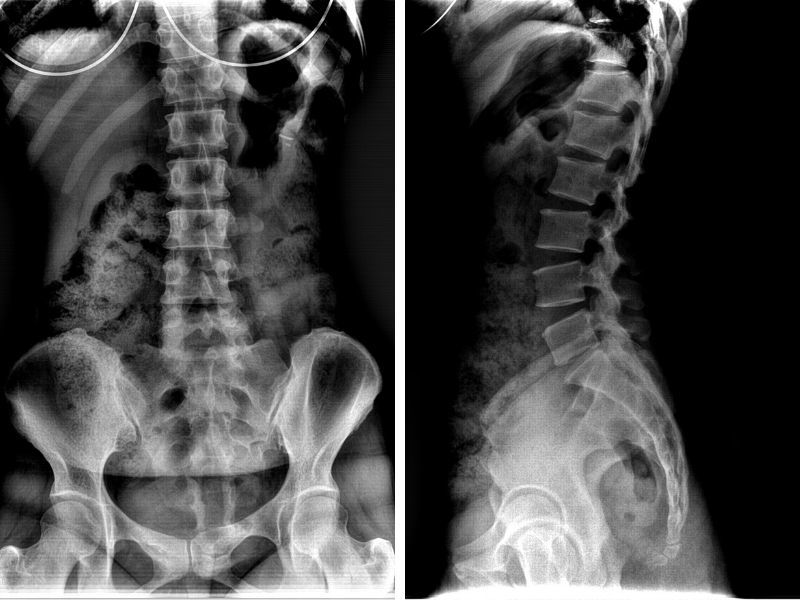

– Chẩn đoán hình ảnh

Nhờ có chụp X-Quang, bác sĩ sẽ đánh giá chính khác vùng viêm khớp chậu, các tổn thương cột sống hay viêm khớp háng mà người bệnh mắc phải. Tuy nhiên, X-Quang không phải là phương pháp đem đến tính chính xác cao và chẩn đoán sớm được tổn thương cấu trúc ở giai đoạn sớm. Do đó, xét nghiệm hình ảnh bằng cách chụp cộng hưởng từ sẽ đưa ra đánh giá chính xác, phát hiện sớm hơn tổn thương cấu trúc và khẳng định loại trừ bệnh viêm cột sống dính khớp.